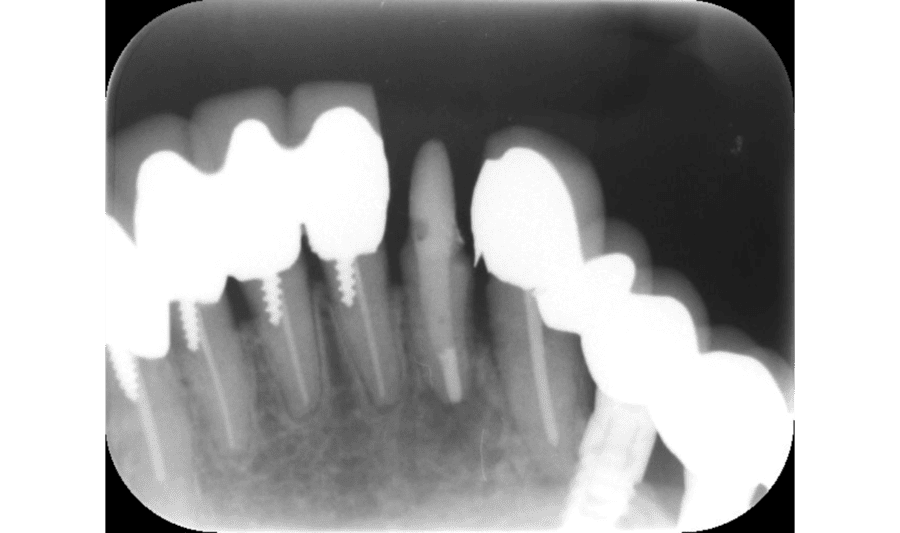

After

根管充填後(約2週間後)